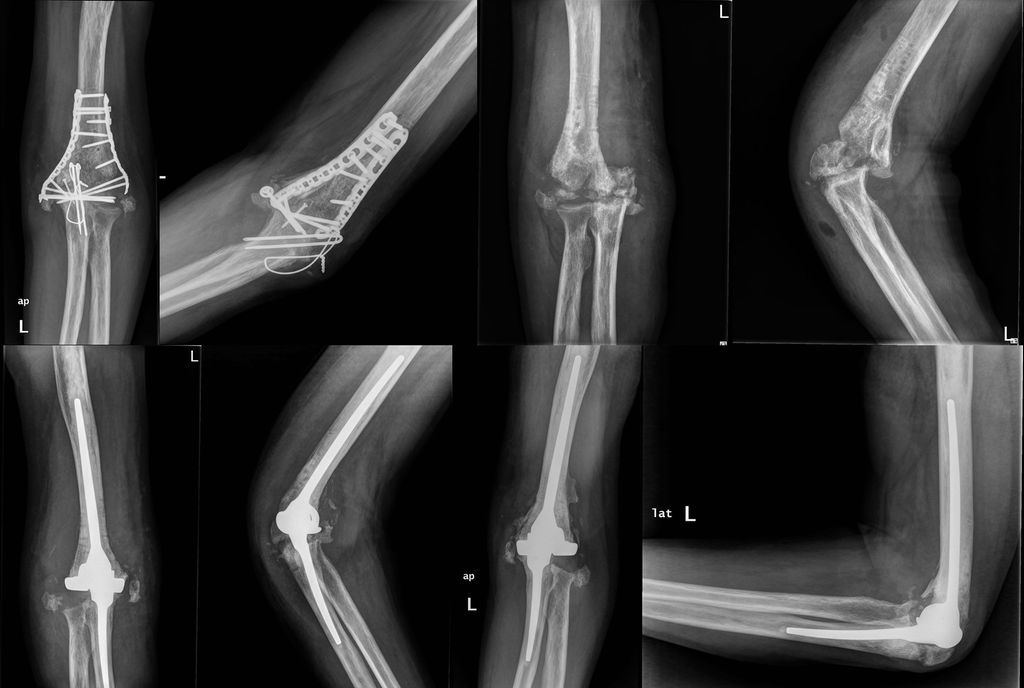

in 2 Fällen eine sehr schwere Steife bis 30°: in 1 Fall Steife in voller Streckung (Abb.1), im zweiten Fall Steife in 70°–80° Flexion

Abb. 1: Ein 42-jähriger männlicher Patient mit distaler Humeruspseudoarthrose und steifem Ellbogen in voller Streckung (a, b). Anamnestisch in dreimaligen Voreingriffen eine infektiöse Komplikation bekannt. Aufgrunddessen hier ein zweizeitiges Vorgehen. Im ersten Schritt die komplette Metallentfernung, Gewebeentnahme für Kultur und PCR-Untersuchung, radikales Debridement und ausgedehnte Arthrolyse (c, d). Bei nachgewiesener Infektionsfreiheit nun die Implantation einer Ellenbogenendoprothese (e, f). Röntgenkontrolle nach 6 Jahren (g, h)